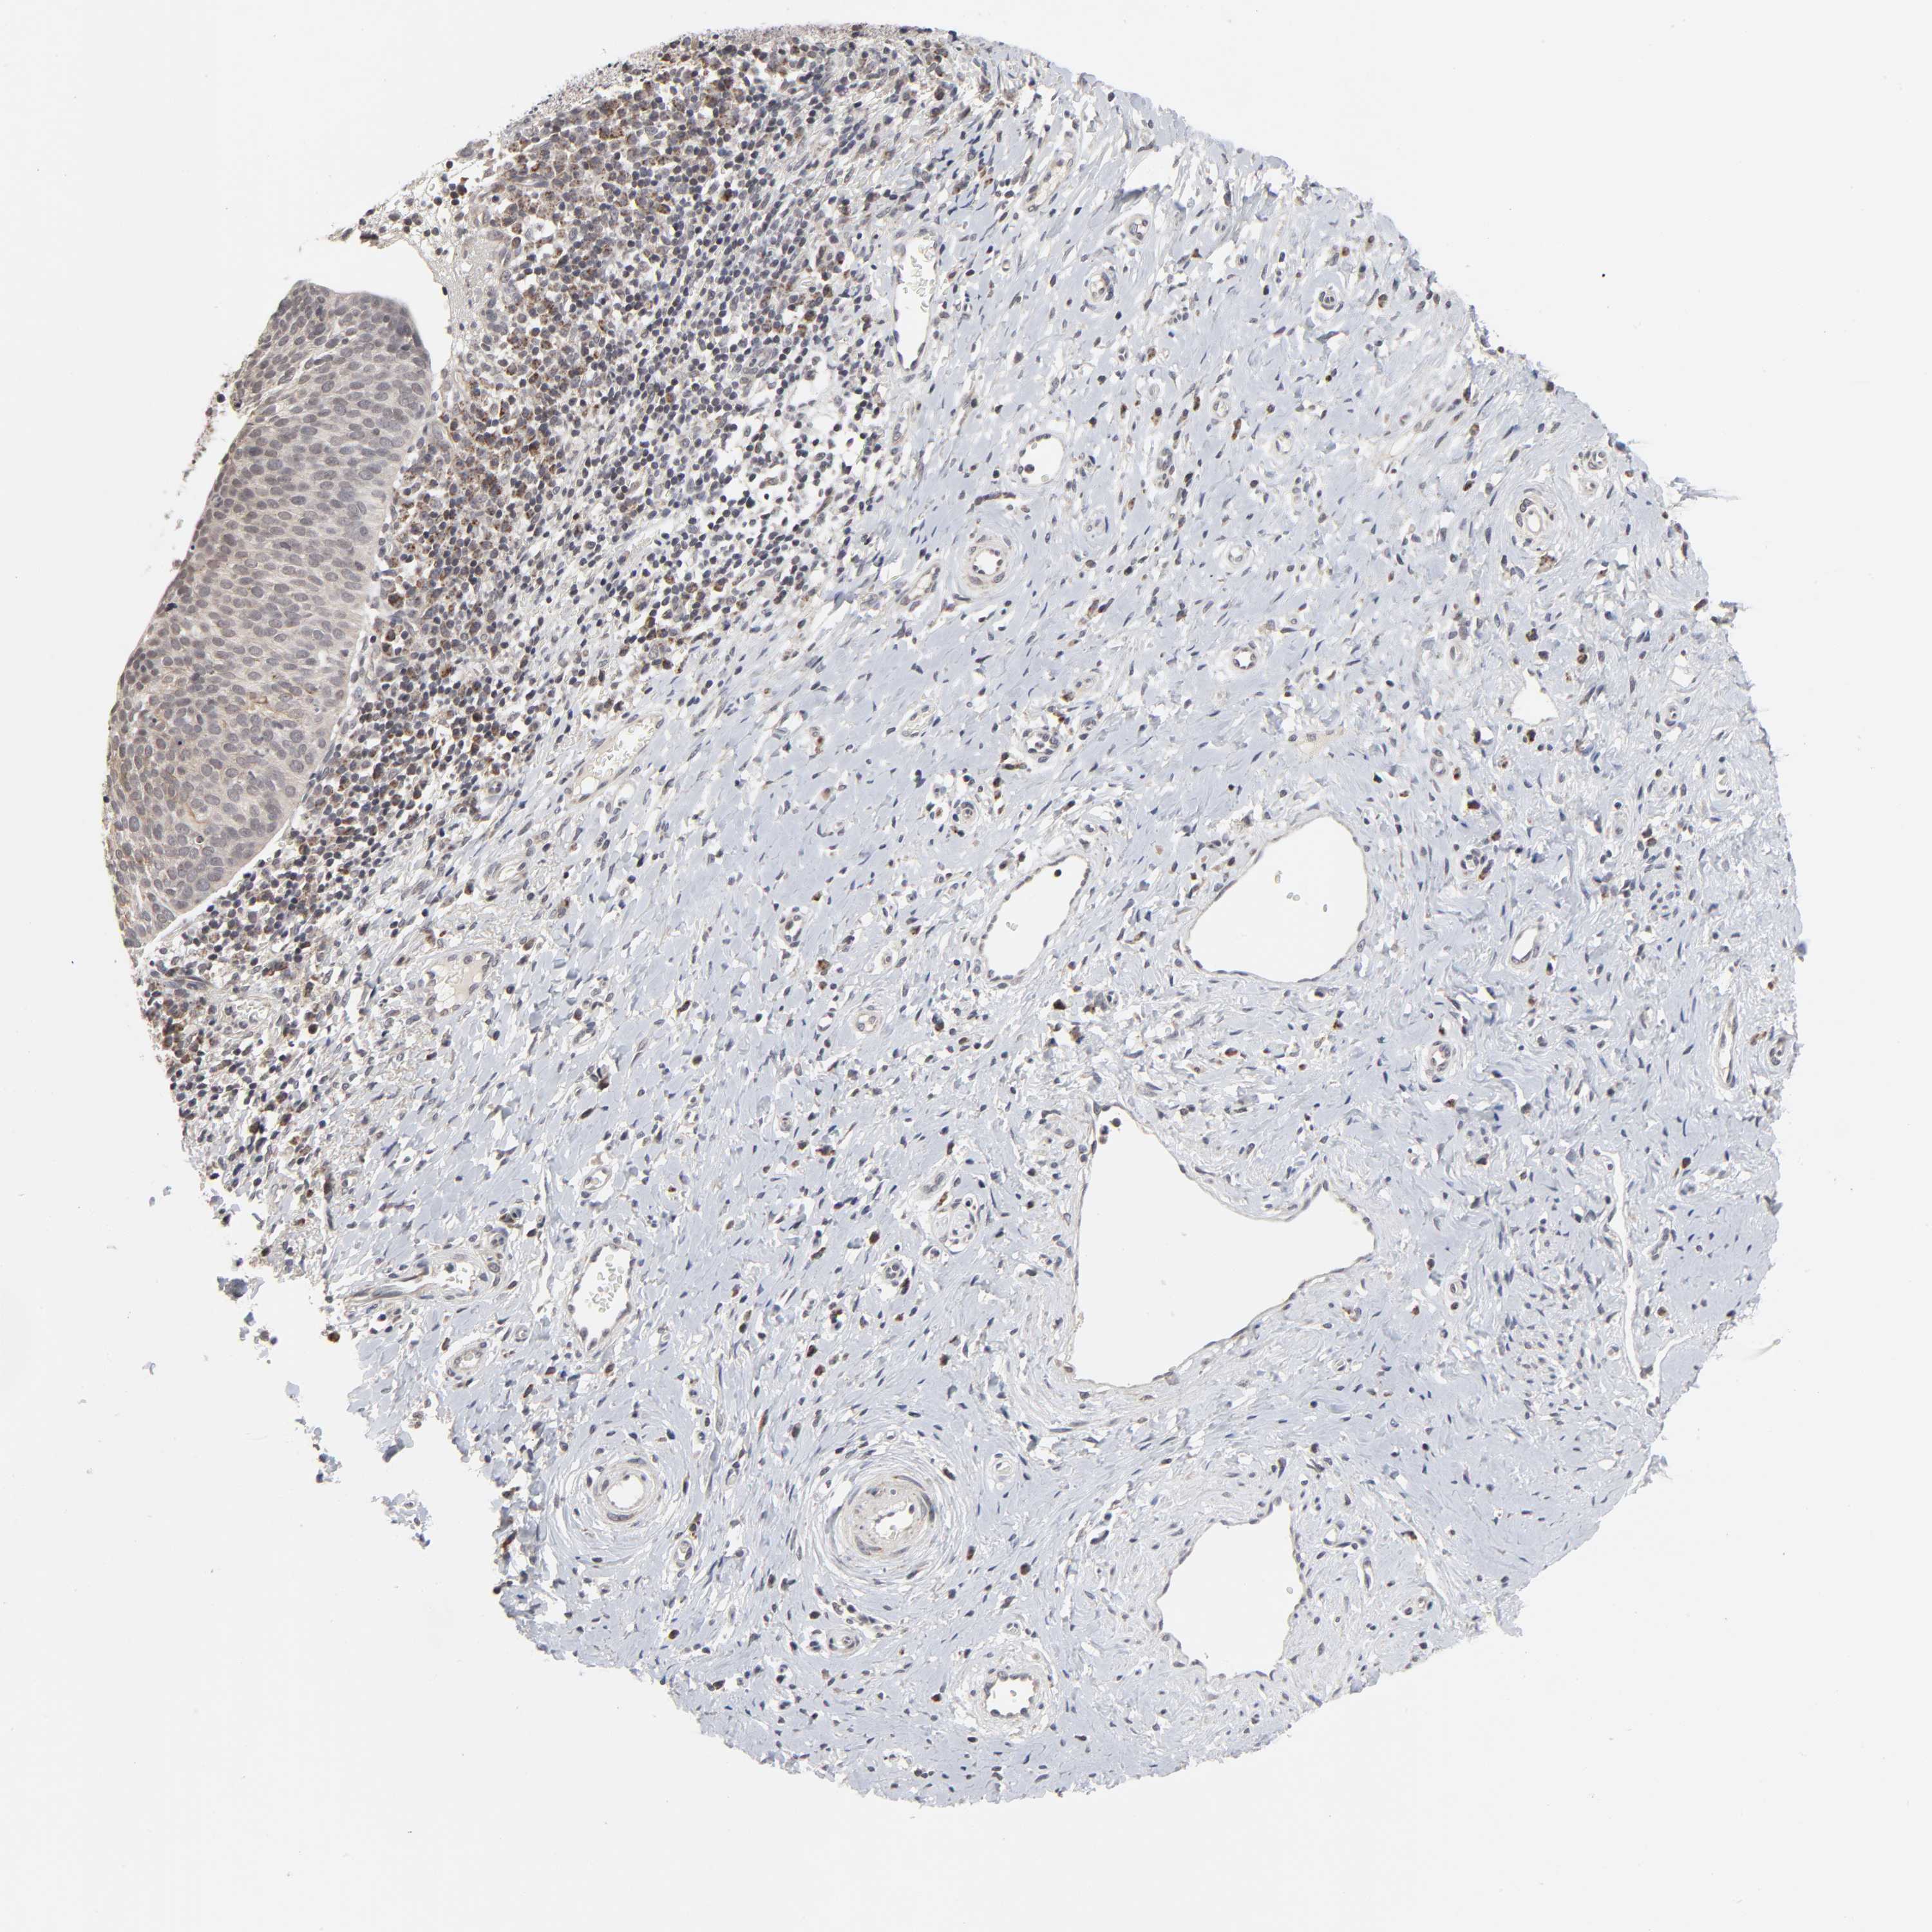

CERVICAL CANCER - Protein expressioni

A mouse-over function shows sample information and annotation data. Click on an image to view it in a full screen mode. Samples can be filtered based on level of antibody staining by selecting one or several of the following categories: high, medium, low and not detected. The assay and annotation is described here.

Note that samples used for immunohistochemistry by the Human Protein Atlas do not correspond to samples in the TCGA dataset.

Antibody stainingi

Antibody staining in the annotated cell types in the current human tissue is reported as not detected, low, medium, or high, based on conventional immunohistochemistry profiling in selected tissues. This score is based on the combination of the staining intensity and fraction of stained cells.

Each image is clickable and will lead to virtual microscopy that enables deeper exploration of all samples and also displays staining intensity scores, fraction scores and subcellular localization as well as patient and tissue information for each sample.

Antibody HPA004171

Staining

High

Medium

Low

Not detected

Intensity

Strong

Moderate

Weak

Negative

Quantity

>75%

75%-25%

<25%

None

Location

Nuclear

Cytoplasmic/membranous

Cytoplasmic/membranous,nuclear

Squamous cell carcinoma, NOS

Adenocarcinoma, NOS